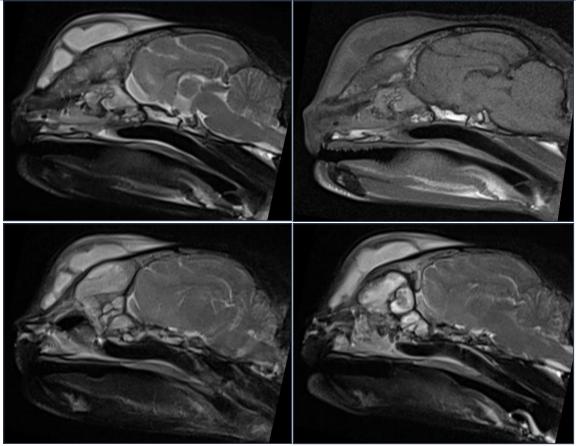

核磁↓↓

核磁结果显示:双侧鼻腔、额窦及额前部皮下可见T1WI等信号、T2WI高信号内容物;双侧局灶

性鼻甲纹理缺失,右侧鼻腔较明显,且右侧鼻骨局灶性溶解;左侧额骨增厚,额窦腔隙较小;腹侧筛板影像不清,双侧嗅球部脑膜T2WI信号增强。小脑尾侧部分实质突入枕骨大孔。双侧鼓室呈T1WI、T2WI低信号,鼓泡壁平滑。